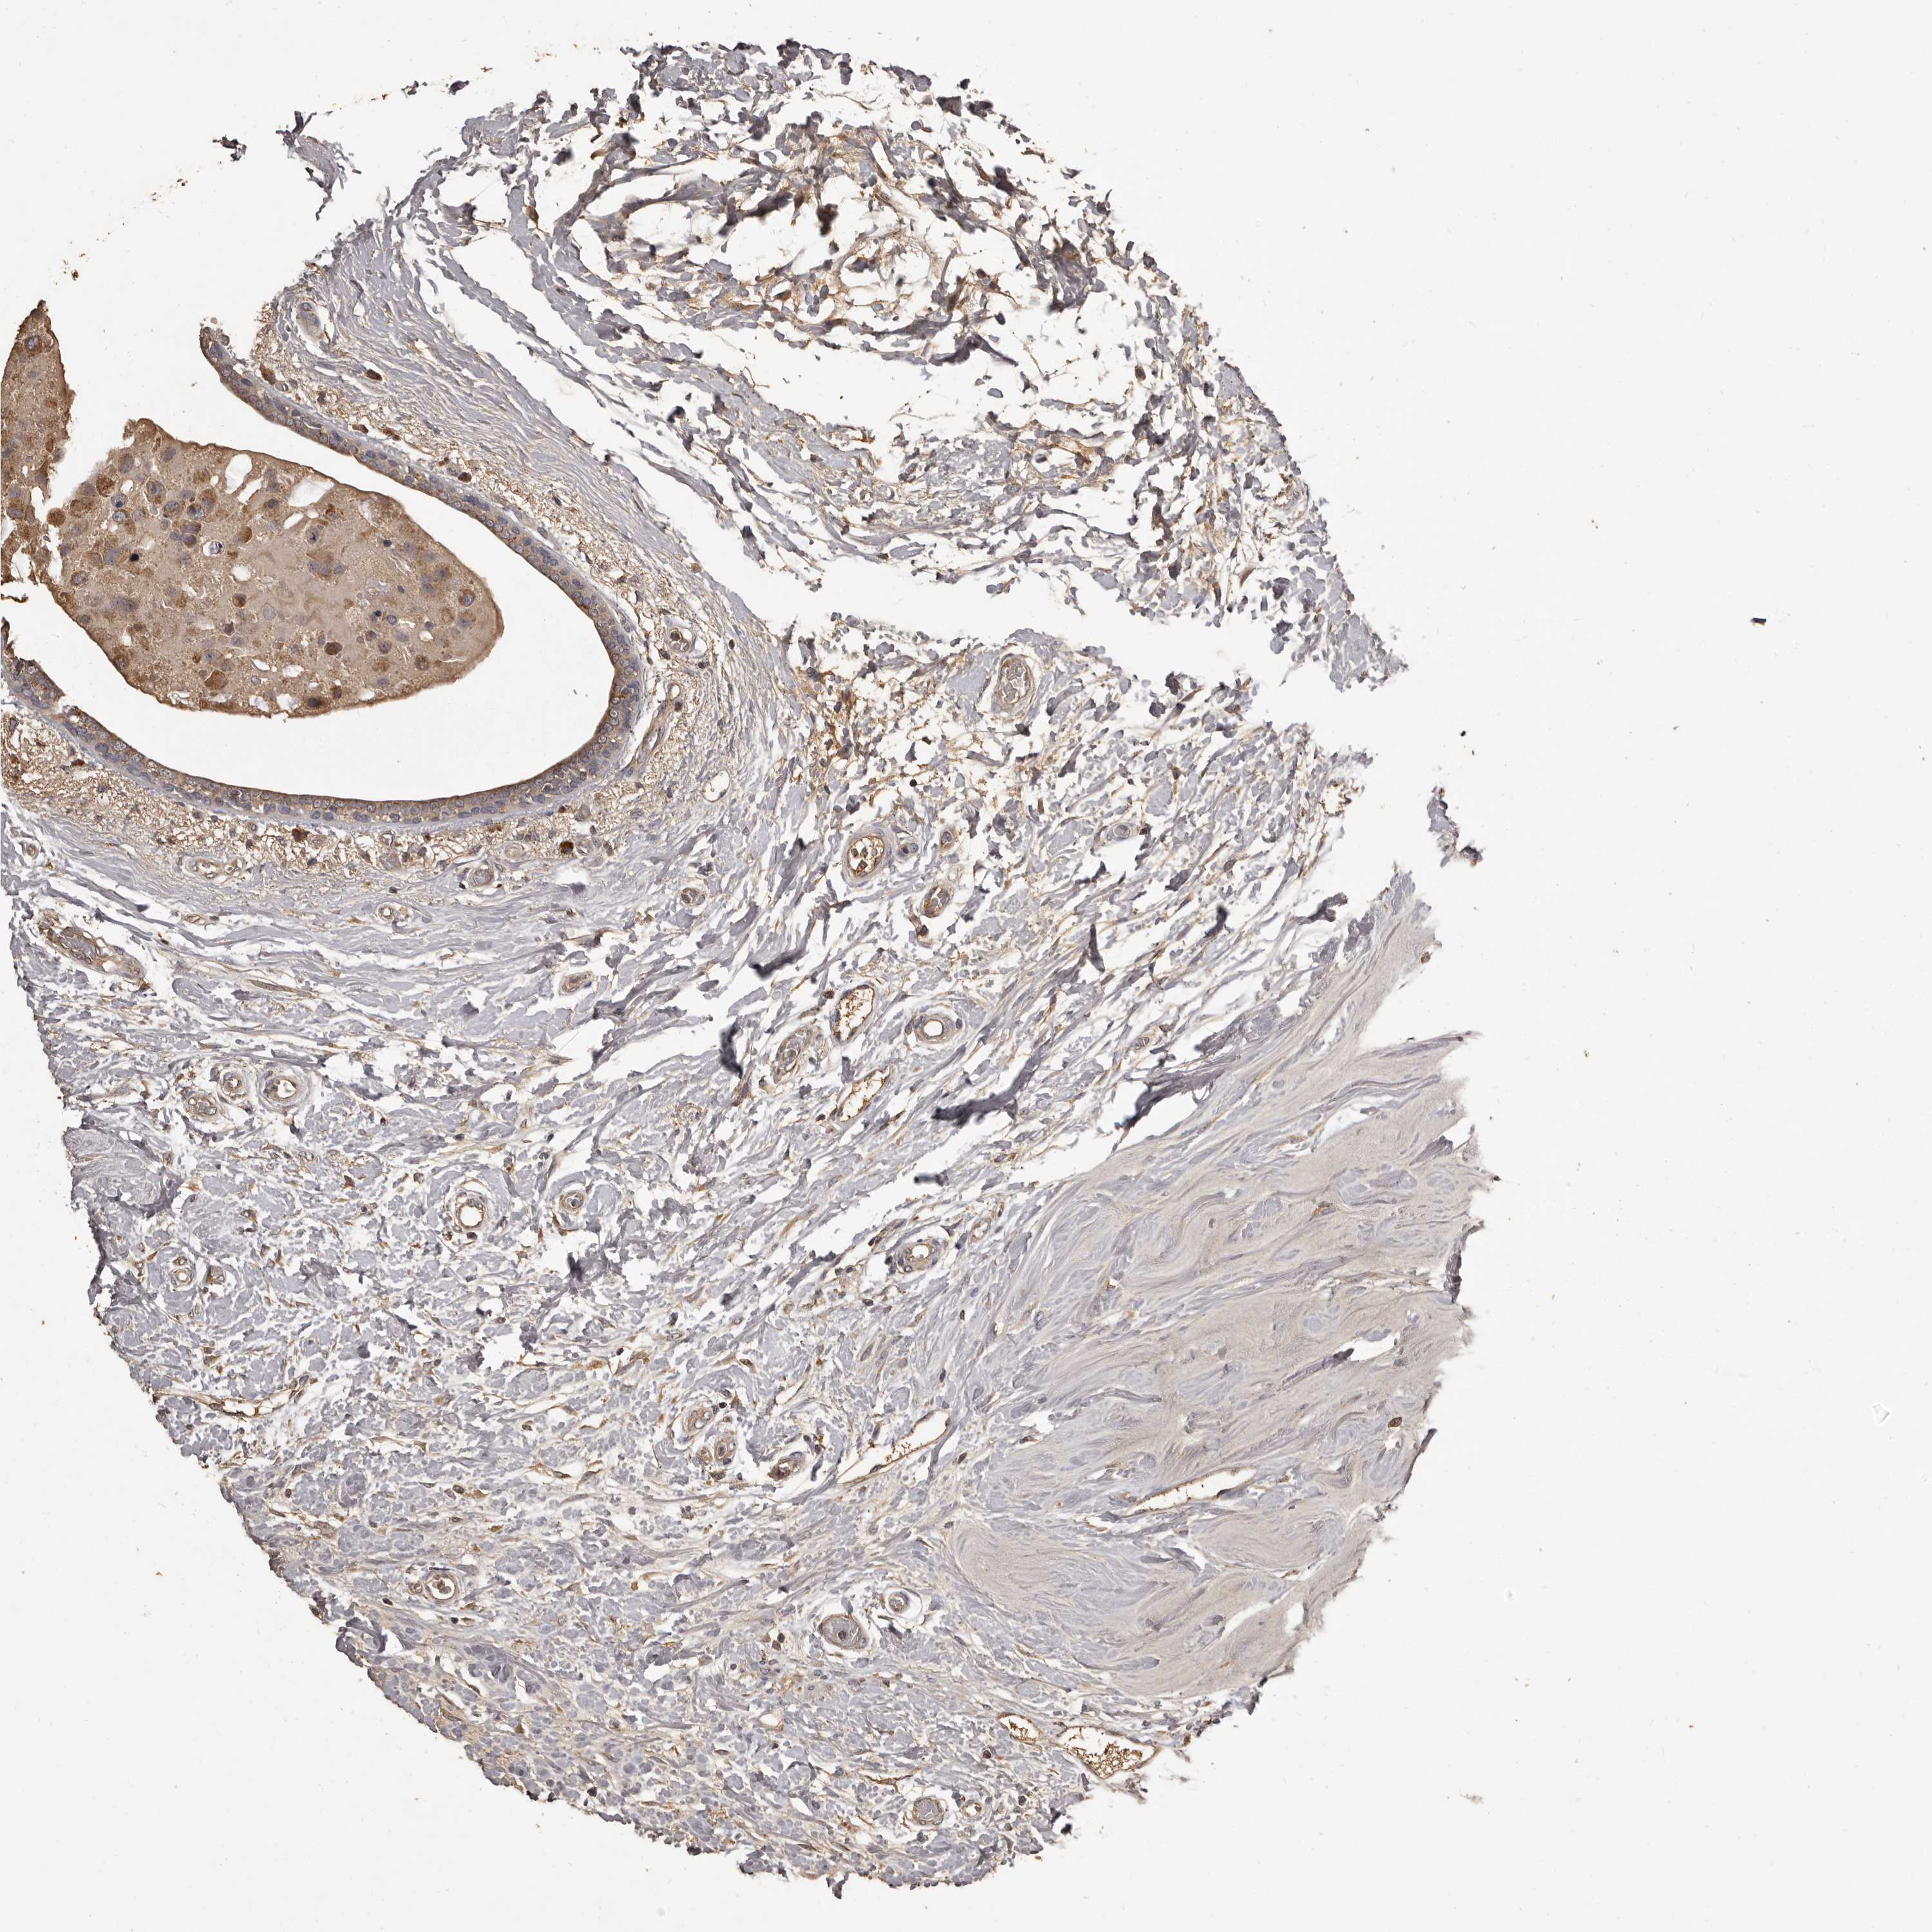

CANCER BREAST CANCER Show tissue menu

BRCA TCGA BRCA VALIDATION PROTEIN EXPRESSION

ANTIBODIES

AND

VALIDATION